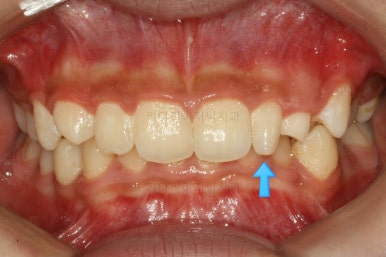

마찬가지로 부산교정치과 키다리아저씨치과에 처음 내원하셨을 당시의 입안 모습입니다.

화살표로 표시된 치아가 작은 앞니 부분인데 크기가 매우 작고 뾰족한 것을 볼 수 있어요. 유치가 아니고 평생 써야 하는 영구치입니다. 이러한 상태를 "왜소치"라고 표현하는데, 치아 크기의 문제로 여러 가지 문제점이 생길 수 있어요.

또 다른 문제는 위아래 앞니가 매우 많이 겹쳐져 있어서 아래 앞니가 거의 보이지 않는다는 점입니다.

미적인 문제 뿐만이 아니라 기능적인 문제도 만들어낼 수 있어서 고쳐주는 것이 좋아요.